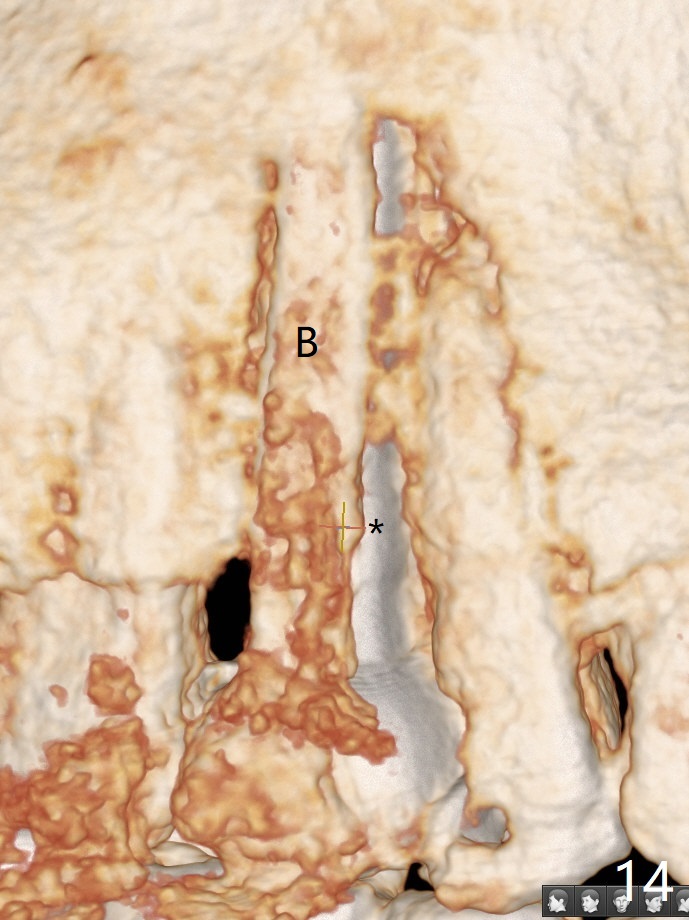

In fact there is a small buccal fistula, which is communicated with the underlying implant threads. Although preop CT shows that the buccal crest is lower than the palatal (3.8x13 mm, Fig.10 P) one, intraop finding of missing buccal plate should dictate a shorter implant (Fig.11) or onlay graft to avoid periimplantitis. Regeneration of the bone plate is limited. Later the fistula disappears with formation of a concavity (Fig.13). There is no symptom. Is bone graft necessary with a remote incision? 3-D images of CT taken 1 year 5 months post cementation show possible mesiobuccal and distopalatal bony defects (Fig.13-16). It is possible that bone graft was placed enough palatal (Fig.16). DO composite at #3 is redo satisfactorily (Fig.17 *).